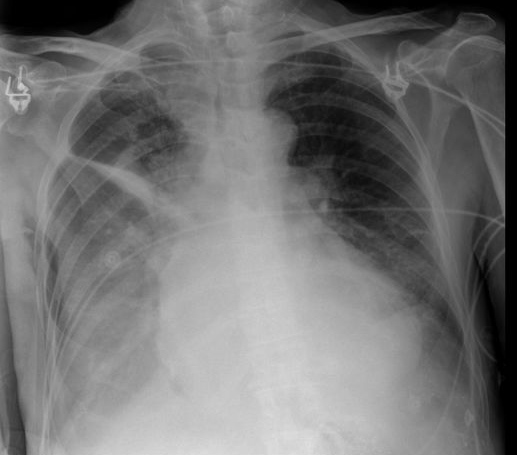

MO Distres respiratorio del adulto por trauma.